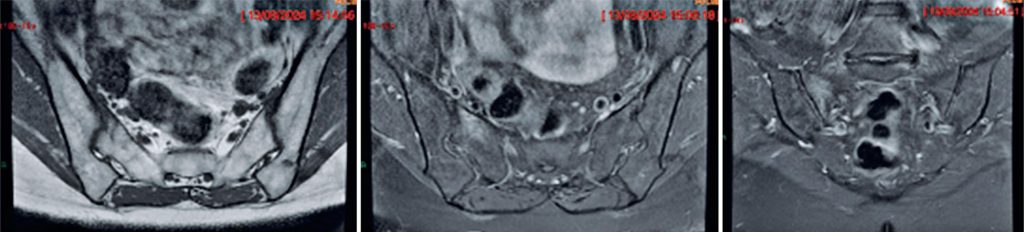

Figure 4

Axial T1, axial T2 with fat suppression, and coronal T2 with fat suppression MRI images showing an incomplete vertical fracture line without displacement on the anterior aspect of the right sacral ala, surrounded by mild bone edema, indicative of a subacute stress reaction